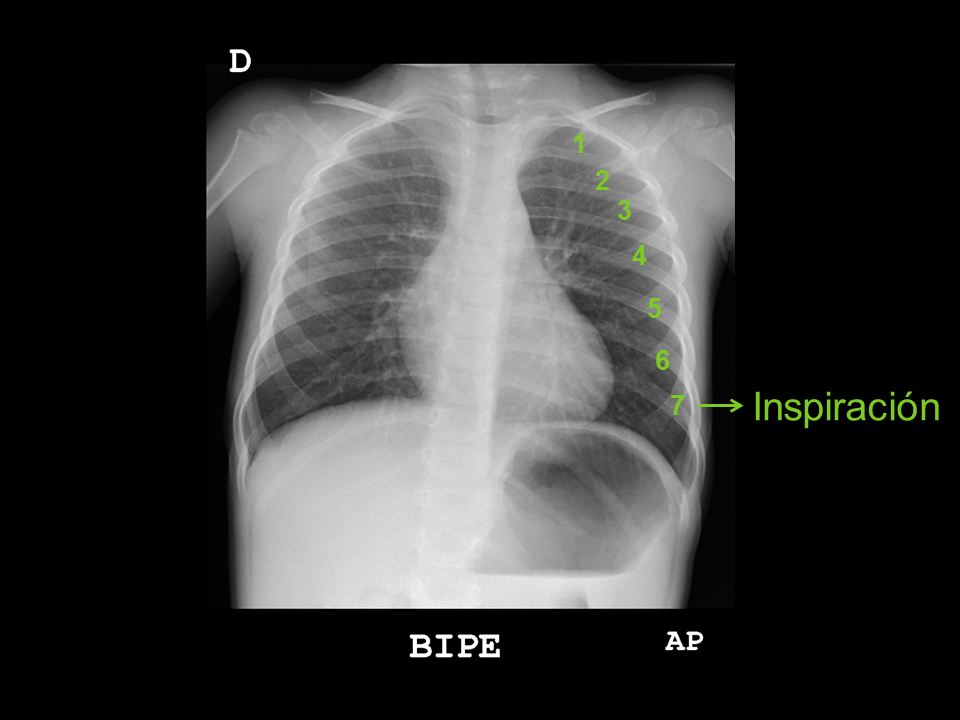

• Grado de inspiración: las cúpulas diafragmáticas deben estar a la altura del sexto arco costal anterior, o del octavo posterior.